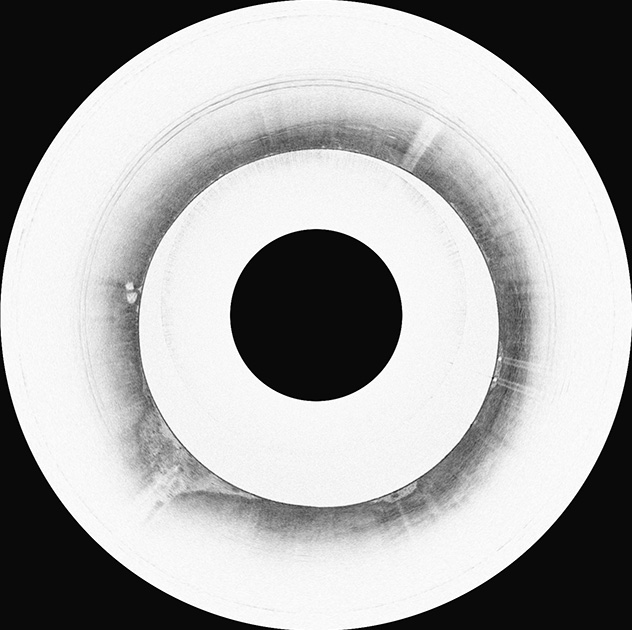

This image of a resected tissue sample (H&E stain) from a gastric muscle biopsy shows muscularis propria and myenteric ganglia.

In collaboration with Mayo Clinic gastroenterologists Gianrico Farrugia, M.D., and Madhusudan (Madhu) Grover, M.B.B.S., our lab has worked extensively to identify a readily available effective and safe endoscopic technique to biopsy the deep muscle layer of the gut wall for evaluation of the enteric nervous system, immune cells and ICCs. Current routine biopsies are superficial and don't contain muscle tissue for analysis.

We developed an innovative technique to obtain deep muscle biopsies from the stomach in order to provide insights into the pathogenesis of gastroparesis. Our ongoing efforts are focused on further refining the endoscopic approach to obtain deep muscle biopsies from the gastrointestinal tract. Our goal is to advance knowledge of the pathophysiology of gastrointestinal motility disorders, leading to potential targeted and curative therapies.